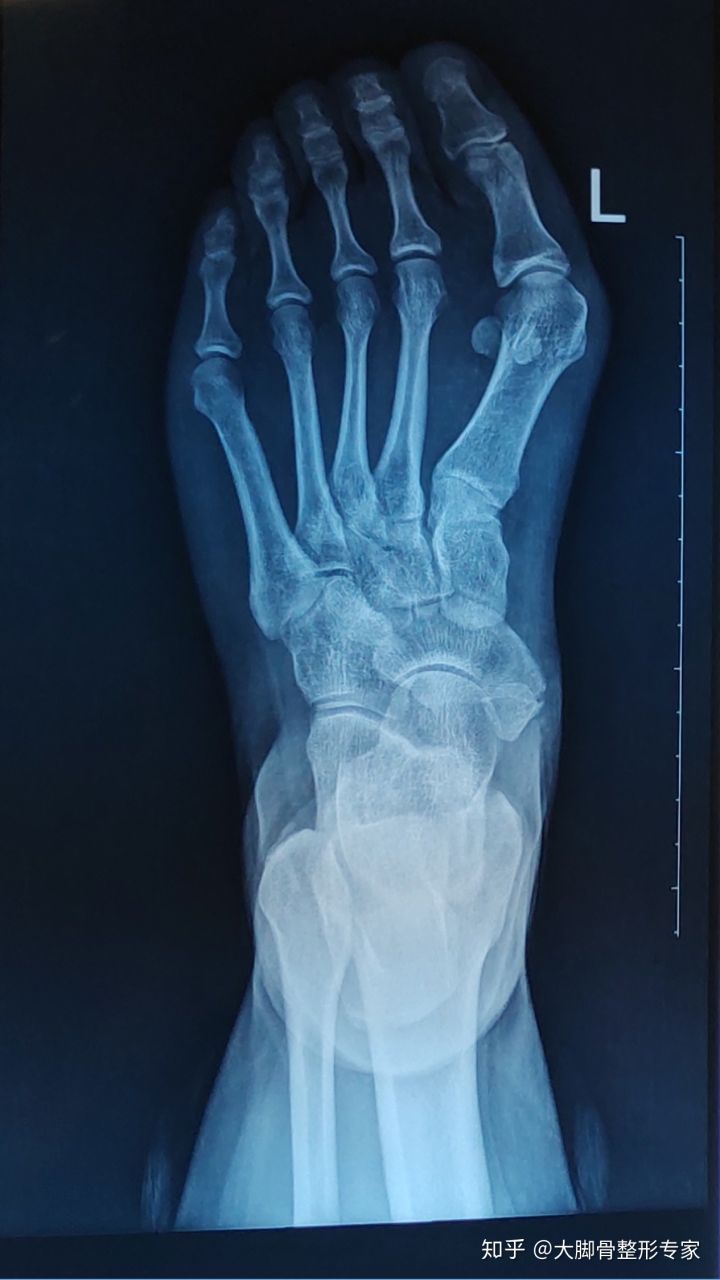

题主小拇趾外侧有个明显的凸起,摸上去硬邦邦的,这个俗称小脚骨,我们看到的外观其实是里面骨头的原因,如下图:

大脚骨和小脚骨X光片

究其原因是里面的第五跖骨向外侧偏斜,与向内侧偏斜的第五趾骨形成犄角,表现出来的就是小脚骨。如下图所示,请看造成局部凸起是因为本该在中轴线上的骨头形成了犄角。

拇外翻是里面的骨头长歪了